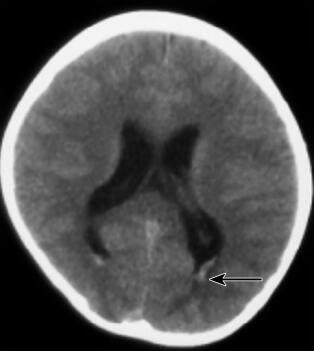

患儿,女,10岁,因“3个月内抽搐2次”于2010年10月23日入本院儿内科。患儿于入院前3个月(2010年7月21日),无明显诱因出现头痛,头痛后出现抽搐,抽搐表现为意识丧失、双眼紧闭、头后仰、全身僵直、双手握拳屈曲、小便失禁,持续约1~2分钟后自行缓解,缓解后意识清楚、全身发软,伴呕吐数次,为非喷射性,呕吐物为胃内容物,发病1天后出现头痛、腰背部疼痛,不伴有发热、腹泻。就诊于当地医院,查颅脑MRI及MRA未见明显异常,行腰椎穿刺术未成功,给予地塞米松及其他药物(具体不详)治疗后好转,未再出现抽搐及头痛。本次入院前3天(2010年10月20日)患儿诉咽痛,无发热、呕吐、腹泻,自服小儿氨酚烷胺颗粒治疗,于当日夜间再次出现抽搐,表现同前,抽搐后亦出现头痛、呕吐及颈项强直,就诊于某市级儿童医院,查颅脑CT检查(图1),显示“脑室系统饱满,双侧脑室后角室管膜下血管影显著,余颅脑平扫未见异常”;血常规、血生化及血气分析检查均未见明显异常。给予头孢甲肟、甘露醇、布洛芬等治疗,仍有间断头痛,为求进一步诊治就诊于本院,门诊以“抽搐原因待查”收入院。

图1 首次颅脑CT检查(外院,2010年10月20日):脑室系统饱满,双侧脑室后角室管膜下血管影显著(箭头),余颅脑平扫未见异常